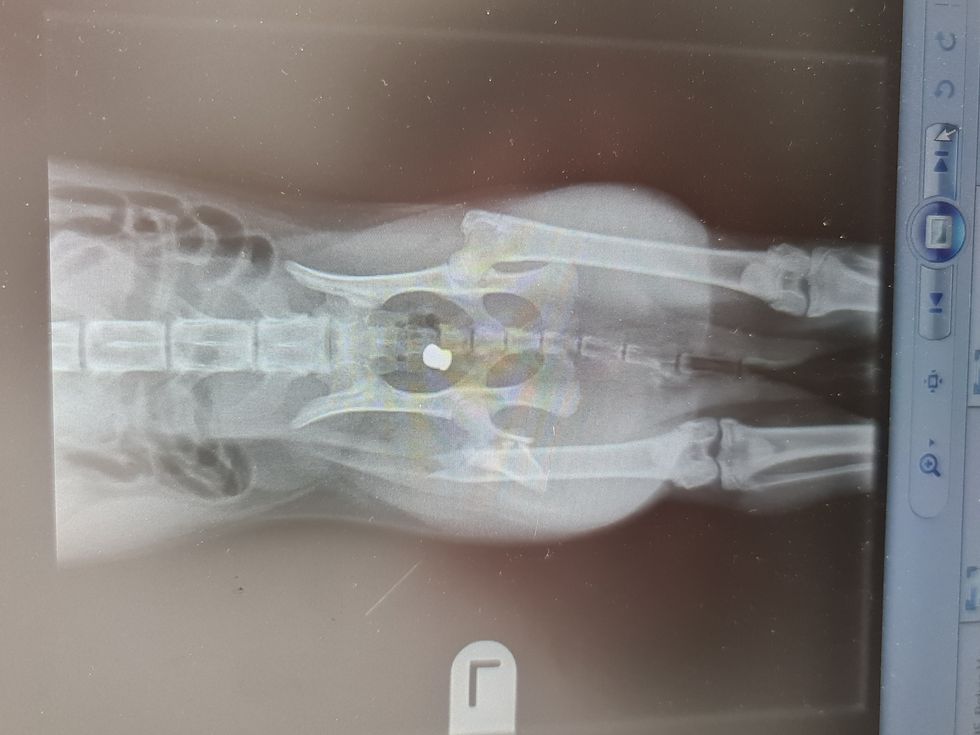

The most recent incident in Acre Close took place on New Year’s Day when 11-year-old cat Frank was shot in his back leg with an air gun.

The damage was extensive with the pellet entering his abdomen.

Frank was rushed to an emergency vet where he required blood transfusions and major surgery at a cost of close to £5,000.

In October 2021, when he was just six months old, Fred was shot in the leg and required emergency medical treatment.

He survived, and was nursed back to health with the pellet still inside him.

However, three months later Fred was shot again and this time the damage was so extensive he had to be put down.